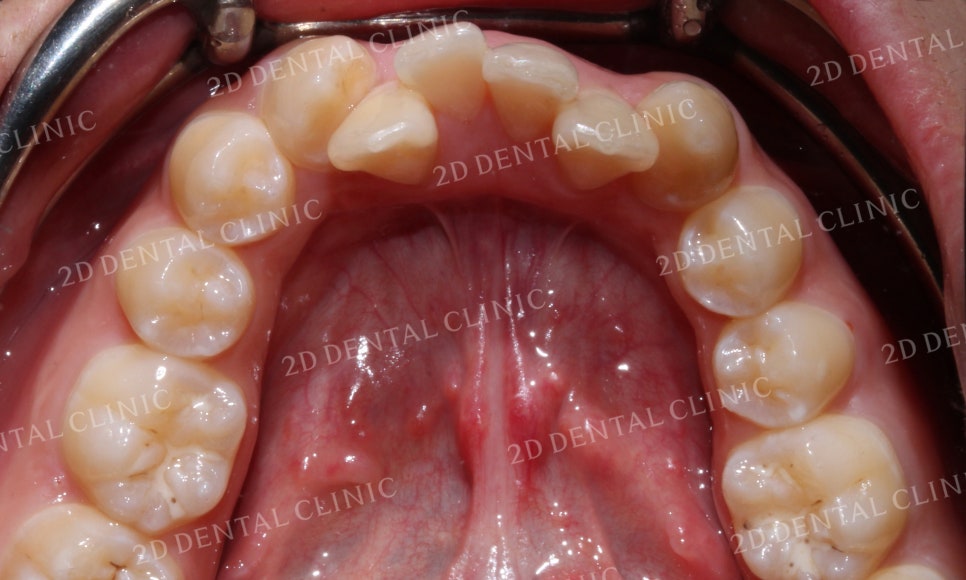

하악의 설측면에서 본 사진은

전치부의 치아들이 구강 내 좁은 공간으로 인해

총생이 심하게 발생한 모습입니다.

이렇게 악궁의 공간이 부족한 경우

치아가 충분히 배열될 수 있도록

악궁을 넓혀주어야 합니다.